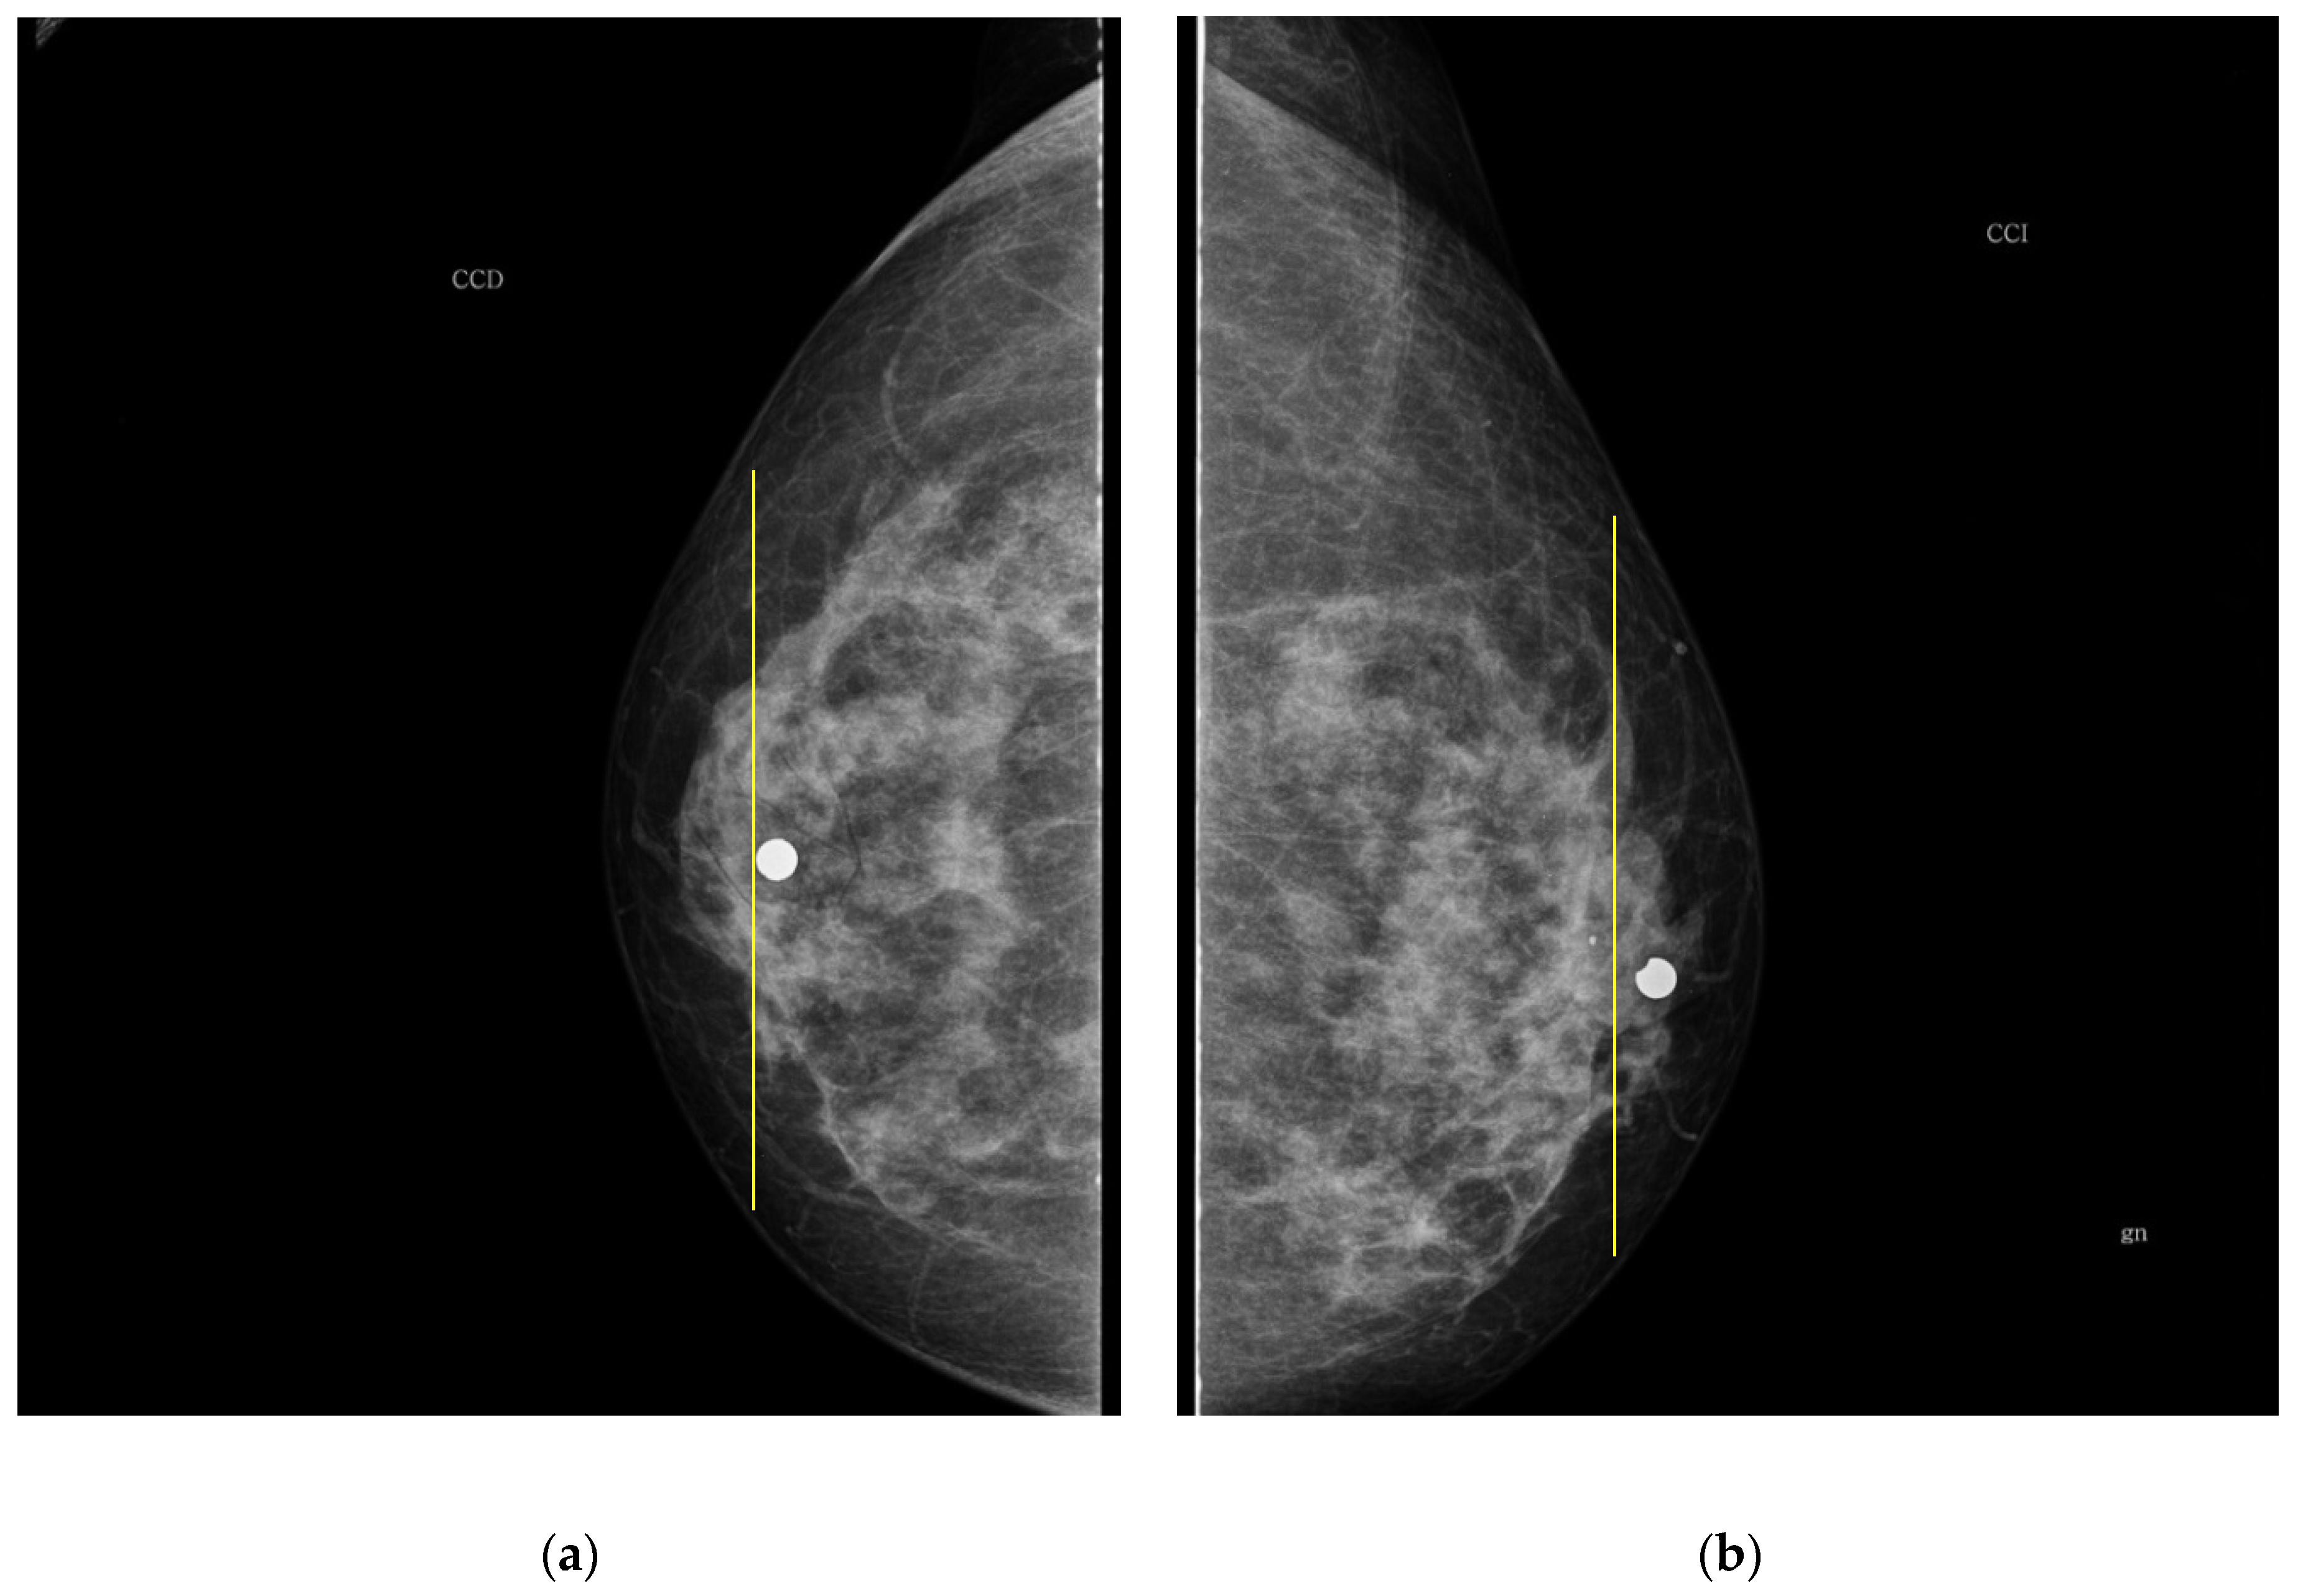

As it is noted, the same BI-RADS PBD for both breasts in all the participants was obtained by the specialist; meanwhile, a 61.5% was achieved by the described ATC clustering. An important uncertainty factor to be considered is that the electrodes ring position in most of the cases is not exactly the same on both breasts for each participant. As a consequence, different bioimpedance values are measured because the breast tissue distribution is not the same. For instance, the specialist evaluation for both breasts in participant 9 is BI-RADS c, while the described ATC classification resulted in BI-RADS b-c and c for the right and left breast, respectively. Such difference may be explained by analyzing the relative electrode ring positions on both breasts. The CC mammogram images of both breasts are shown in Figure 6, where the electrodes ring position is illustrated with a yellow vertical line. As it is observed, the left breast has less adipose tissue than the right breast. This amount of fatty tissue is the reason why a higher bioimpedance value is measured.

Figure 6. CC mammogram images of participant 9 and relative electrode ring position (yellow vertical line): (a) right breast; (b) left breast.